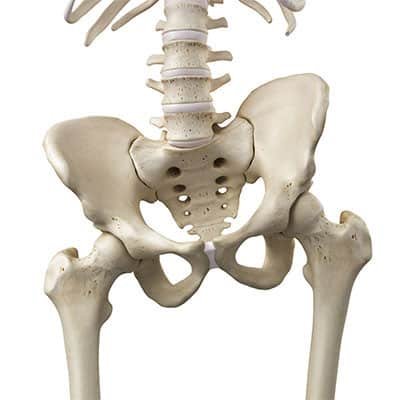

ما هو اعوجاج الحوض (Pelvic Tilt)؟

يشير اعوجاج الحوض أو ما يطلق عليه البعض (دوران الحوض) إلى تغير في الوضع الطبيعي للحوض بحيث يميل إلى الأمام أو الخلف أو إلى أحد الجانبين.

في الوضع الطبيعي يكون الحوض في حالة توازن، بحيث تكون العظام الأمامية والخلفية للحوض في مستوى متقارب يسمح بتوزيع متساوٍ للقوى بين العمود الفقري والعضلات المحيطة به.

عند حدوث اعوجاج الحوض (pelvic tilt) يختل هذا التوازن، مما يؤدي إلى تغير في محاذاة العمود الفقري. نتيجة لذلك قد يضطر الجسم إلى التعويض بزيادة تقوس الظهر أو تغيير طريقة الحركة، وهو ما يفسر ارتباط اعوجاج الحوض بآلام الظهر واضطرابات المشي.